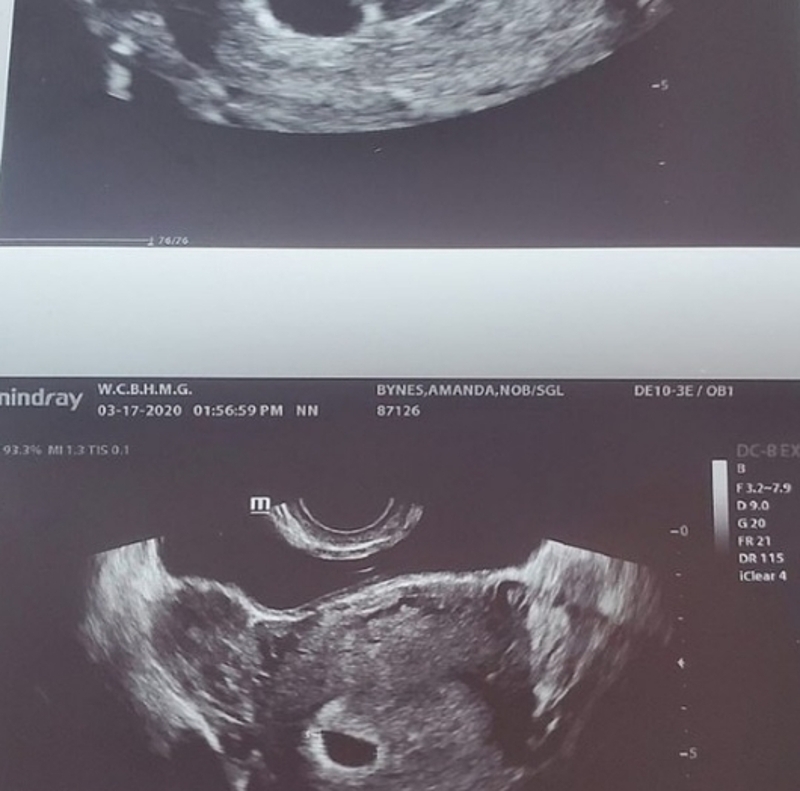

33-летняя звезда фильма «Отличница легкого поведения» и «Лак для волос» Аманда Байнс порадовала своих поклонников новостью о том, что скоро станет матерью. Она и ее жених Пол Майкл всполошили «Инстаграм», одновременно выложив снимок УЗИ.

«Ребенок на борту», — подписала пост артистка. Но юзеры не успели толком поздравить пару, как публикации были поспешно удалены. По какой причине влюбленные решили удалить свои публикации, пока не известно, но инсайдеры подтвердили новость о беременности Байнс и отметили, что девушка невероятно счастлива.